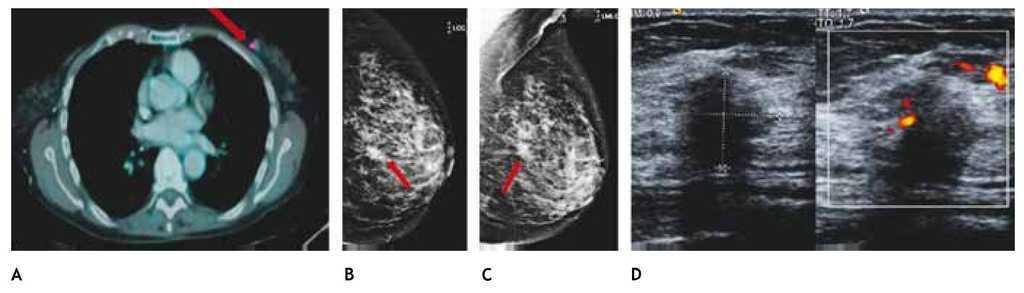

La tomografía por emisión de positrones (PET), la cual fusiona tomografía computada, con estudio de medicina nuclear, es otro método de imagen diagnóstica, morfológico y funcional que permite valorar básicamente la extensión de la enfermedad mamaria maligna. Sin embargo, trabajos recientes mencionan la utilidad en el diagnóstico primario del cáncer mamario con equipos dedicados de mastografía y medicina nuclear (PEM)12.

También ha demostrado ser útil en pacientes con sospecha de enfermedad metastásica sin diagnóstico de cáncer mamario establecido, por lo que se debe realizar mastografía en caso de identificar zonas de hipermetabolismo en el tejido mamario (figs. 11A-D).

Figura 11 A) Paciente de 77 años con antecedente de linfoma no Hodgkin (PET-CT), tumoración mamaria izquierda con captación de 18-FDG (flecha). B) y C) Mastografía con tumoración espiculada en CSEI (flechas). D) Tumoración hipoecoica, irregular y vascularizada, BIRADS 5: cáncer ductal infiltrante.

Diversos estudios12-14 han informado la capacidad del PET-CT para demostrar enfermedad maligna oculta y establecen que este estudio tiene alta sensibilidad para recurrencia (92% al 100%), en comparación con los métodos de exploración convencional, especialmente para metástasis ósea o ganglionar. El PET-CT es menos sensible para recurrencia local que la RM. Es útil en la planeación de la escisión quirúrgica en pacientes con múltiples focos de enfermedad.